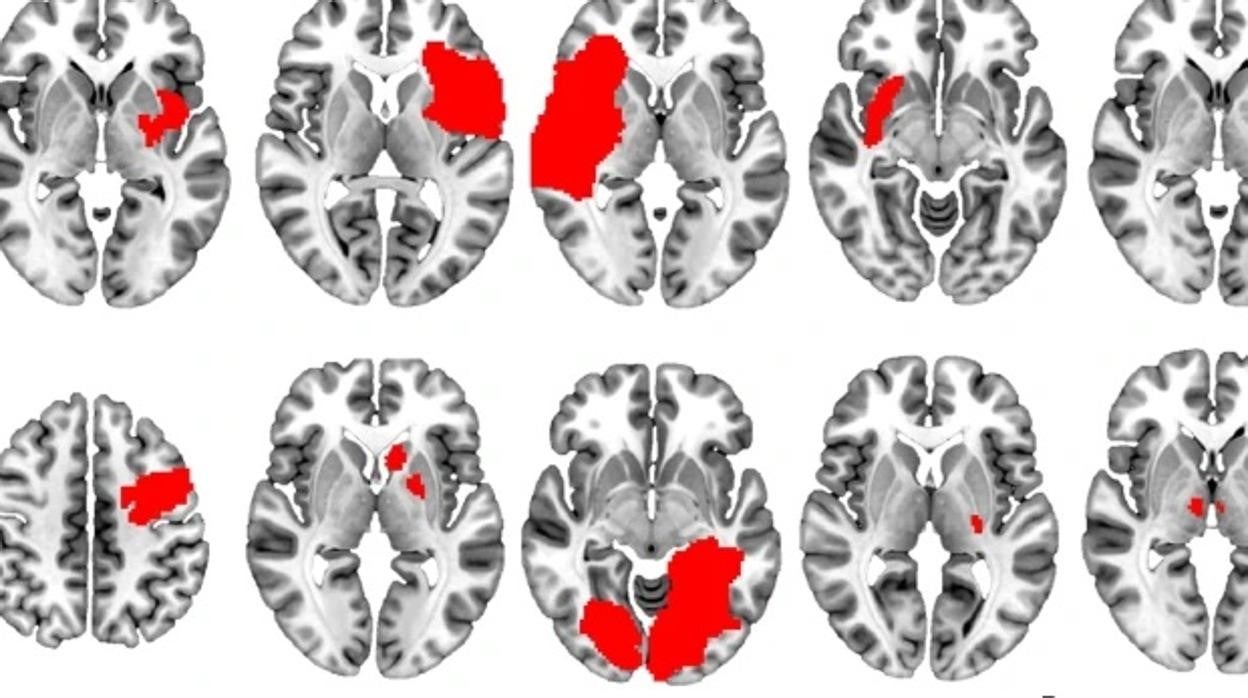

Cada corte representa a un paciente diferente y las ubicaciones de las lesiones se muestran en rojo Nature

Fox y sus colegas utilizaron datos de dos grupos independientes de pacientes adictos a la nicotina que luego sufrieron una lesión cerebral, generalmente causada por un accidente cerebrovascular.

El equipo de Fox comparó las lesiones de los pacientes que no pudieron dejar de fumar con las lesiones resultantes de la remisión de la adicción al tabaco. A continuación, utilizaron una base de datos conocida como el conectoma humano para trazar un mapa de cada lesión en el circuito cerebral más amplio.

Descubrieron que los dos conjuntos de datos de lesiones de fumadores que condujeron a la remisión de la adicción al tabaco se correspondían con un circuito cerebral específico. Para su sorpresa, también descubrieron en un tercer conjunto de datos de lesiones de alcoholismo que la reducción del riesgo de alcoholismo se correspondía con un circuito cerebral similar , lo que sugiere una vía neuronal potencialmente terapéutica y dirigible para la adicción en general, más que para la adicción a una sustancia específica.